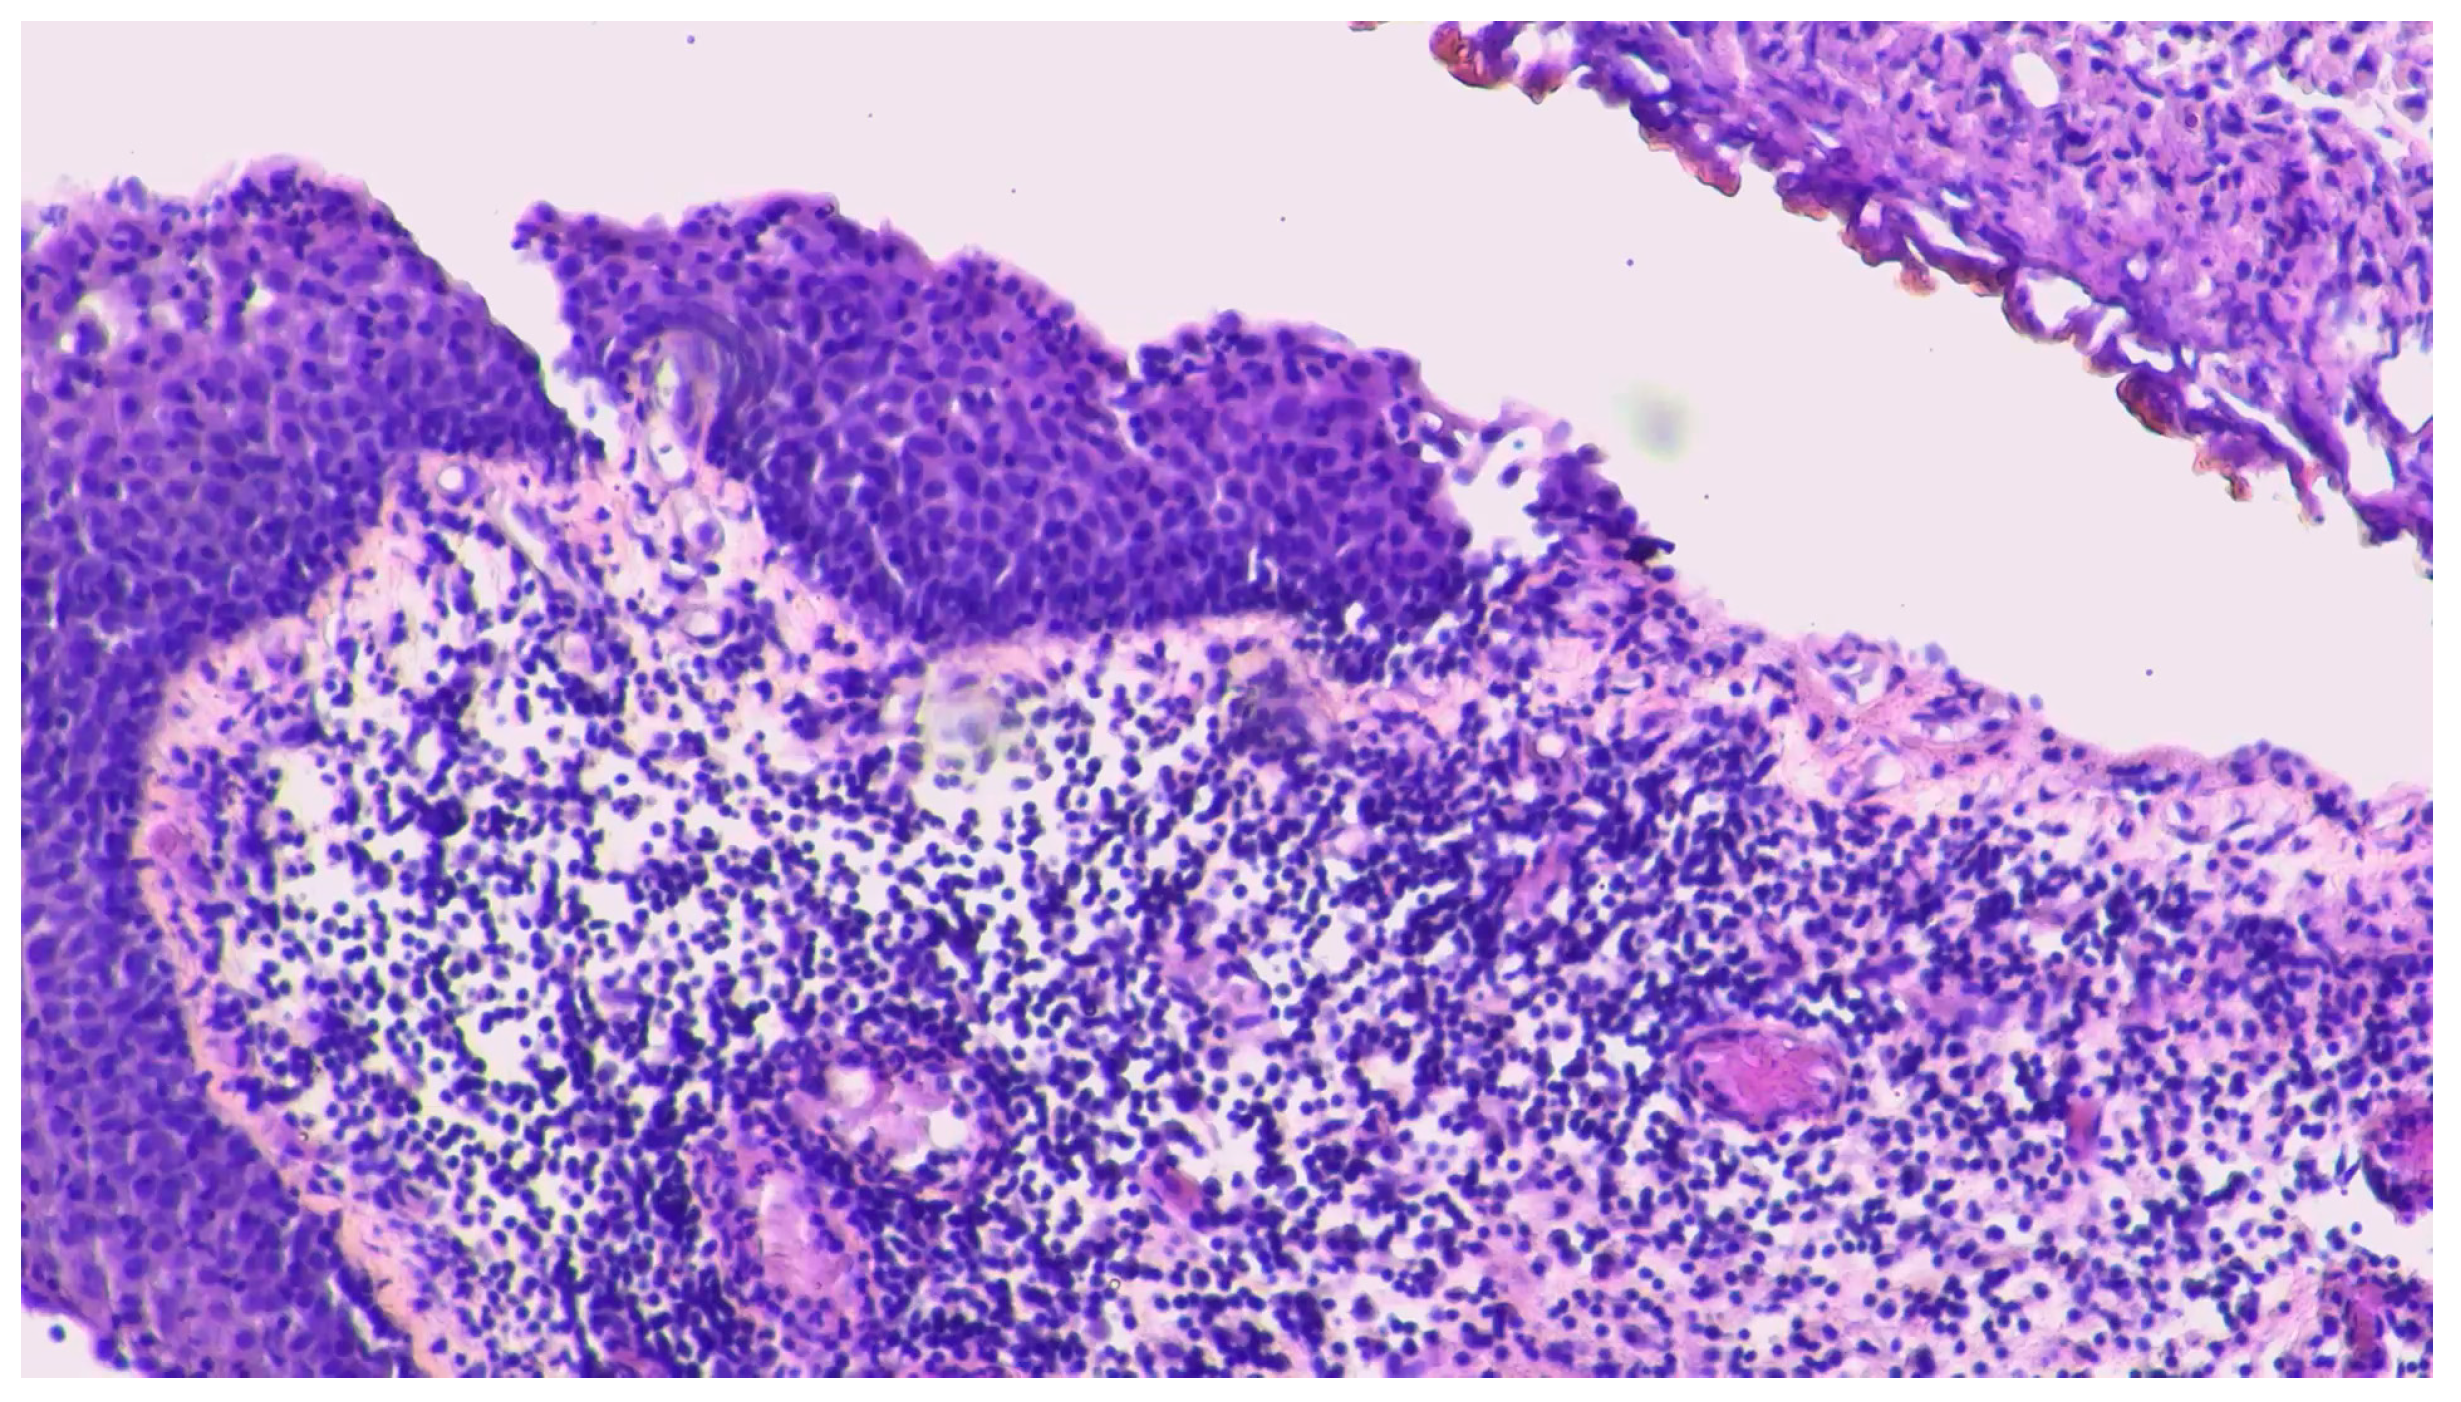

2. Case Report